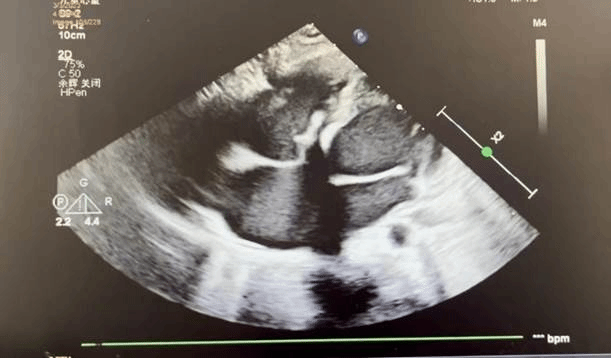

术后超声

心内科修丽丽副主任医师在术中进行超声引导

术前缜密准备,手术如期举行。麻醉科杨旺主治医师为玲玲进行全麻后,在心内科修丽丽副主任医师的全程超声指导下,张东会副主任医师等人凭借默契的配合、精湛的技术,成功完成手术。术后造影及经胸超声结果显示全降解封堵器形态良好,封堵完全,无残余分流,主动脉无返流,遂完全释放封堵器,回收成型线,封堵效果理想。